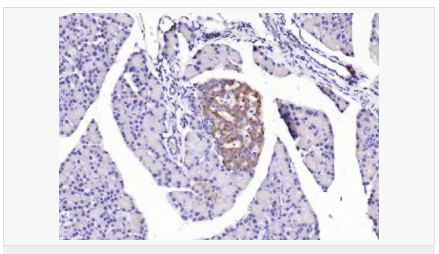

| 產品應用 | WB=1:500-2000 ELISA=1:5000-10000 IHC-P=1:100-500 IHC-F=1:100-500 IF=1:100-500 (石蠟切片需做抗原修復) not yet tested in other applications. optimal dilutions/concentrations should be determined by the end user. |

| 產品介紹 | The protein encoded by this gene is a leucine-rich repeat-containing receptor (LGR) and member of the G protein-coupled, 7-transmembrane receptor (GPCR) superfamily. The encoded protein is a receptor for R-spondins and is involved in the canonical Wnt signaling pathway. This protein plays a role in the formation and maintenance of adult intestinal stem cells during postembryonic development. Several transcript variants encoding different isoforms have been found for this gene. [provided by RefSeq, Sep 2015] Function: Receptor for R-spondins that potentiates the canonical Wnt signaling pathway and acts as a stem cell marker of the intestinal epithelium and the hair follicle. Upon binding to R-spondins (RSPO1, RSPO2, RSPO3 or RSPO4), associates with phosphorylated LRP6 and frizzled receptors that are activated by extracellular Wnt receptors, triggering the canonical Wnt signaling pathway to increase expression of target genes. In contrast to classical G-protein coupled receptors, does not activate heterotrimeric G-proteins to transduce the signal. Involved in the development and/or maintenance of the adult intestinal stem cells during postembryonic development. Subunit: Identified in a complex composed of RNF43, LGR5 and RSPO1. Subcellular Location: Cell membrane; Multi-pass membrane protein Tissue Specificity: Expressed in skeletal muscle, placenta, spinal cord, and various region of brain. Expressed at the base of crypts in colonic and small mucosa stem cells. In premalignant cancer expression is not restricted to the cript base. Overexpressed in cancers of the ovary, colon and liver. Similarity: Belongs to the G-protein coupled receptor 1 family. Contains 16 LRR (leucine-rich) repeats. Contains 1 LRRNT domain. SWISS: O75473 Gene ID: 8549 Database links: Entrez Gene: 8549 Human Entrez Gene: 14160 Mouse Omim: 606667 Human SwissProt: O75473 Human SwissProt: Q9Z1P4 Mouse Unigene: 658889 Human Unigene: 42103 Mouse Unigene: 214063 Rat Important Note: This product as supplied is intended for research use only, not for use in human, therapeutic or diagnostic applications. Lgr5基因(Wnt細胞信號系統)是一種G蛋白偶聯受體,已經被確定為幾種成年組織和癌癥中干細胞的一個獨特標記。Lgr5最初是在結腸癌細胞中發現的,有報道稱:在惡化前的小鼠腺瘤中也有發現,這說明Lgr5很可能也是其他組織成體干細胞和癌癥干細胞的標志物。 |